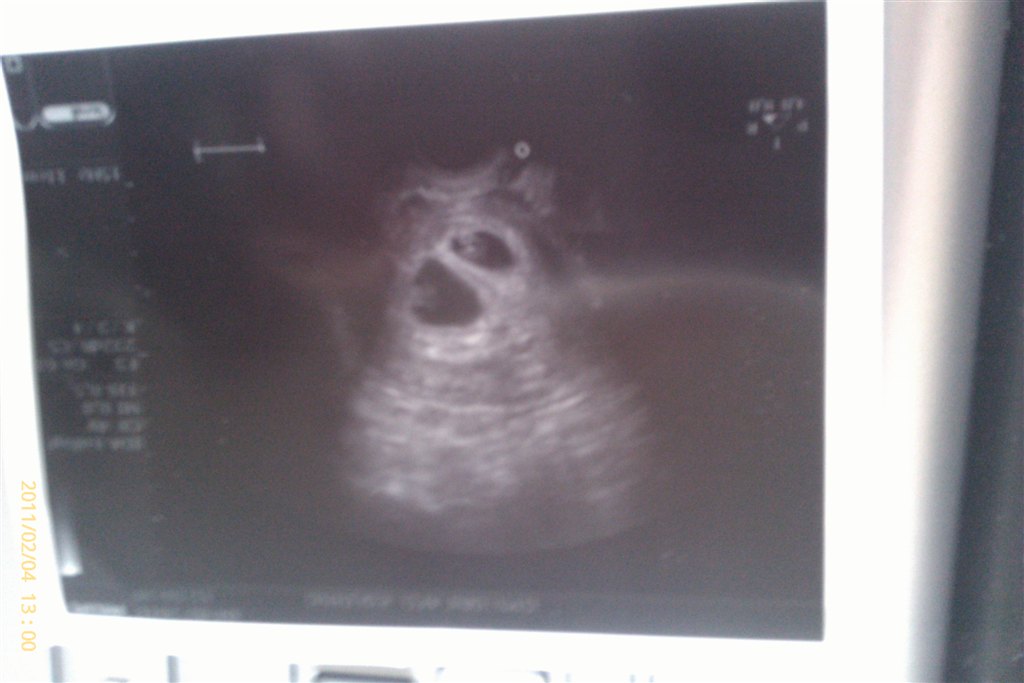

Billed 2: genetisk rådgivning pga. sygdom i familie 10+1